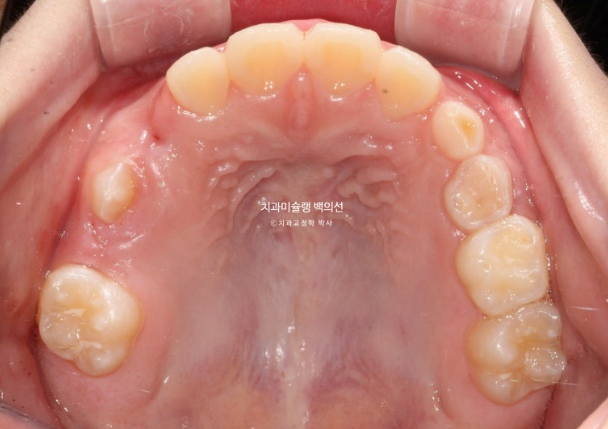

어금니 반대교합은 상악 악궁이 좁아서 생기는 문제입니다.

즉 악궁확장이 필요하고 인비절라인 퍼스트로 악궁확장을 동반하여 MA (mandible advance, 하악전진기능) 기능을 이용한 비대칭 치료가 필요합니다.

어금니 반대교합의 원인은 좁은 상악 악궁에 있습니다.

이제 인비절라인퍼스트 치료로 악궁확장, 앞니배열 등을 먼저 진행하여 교합간섭 해소를 도모합니다.